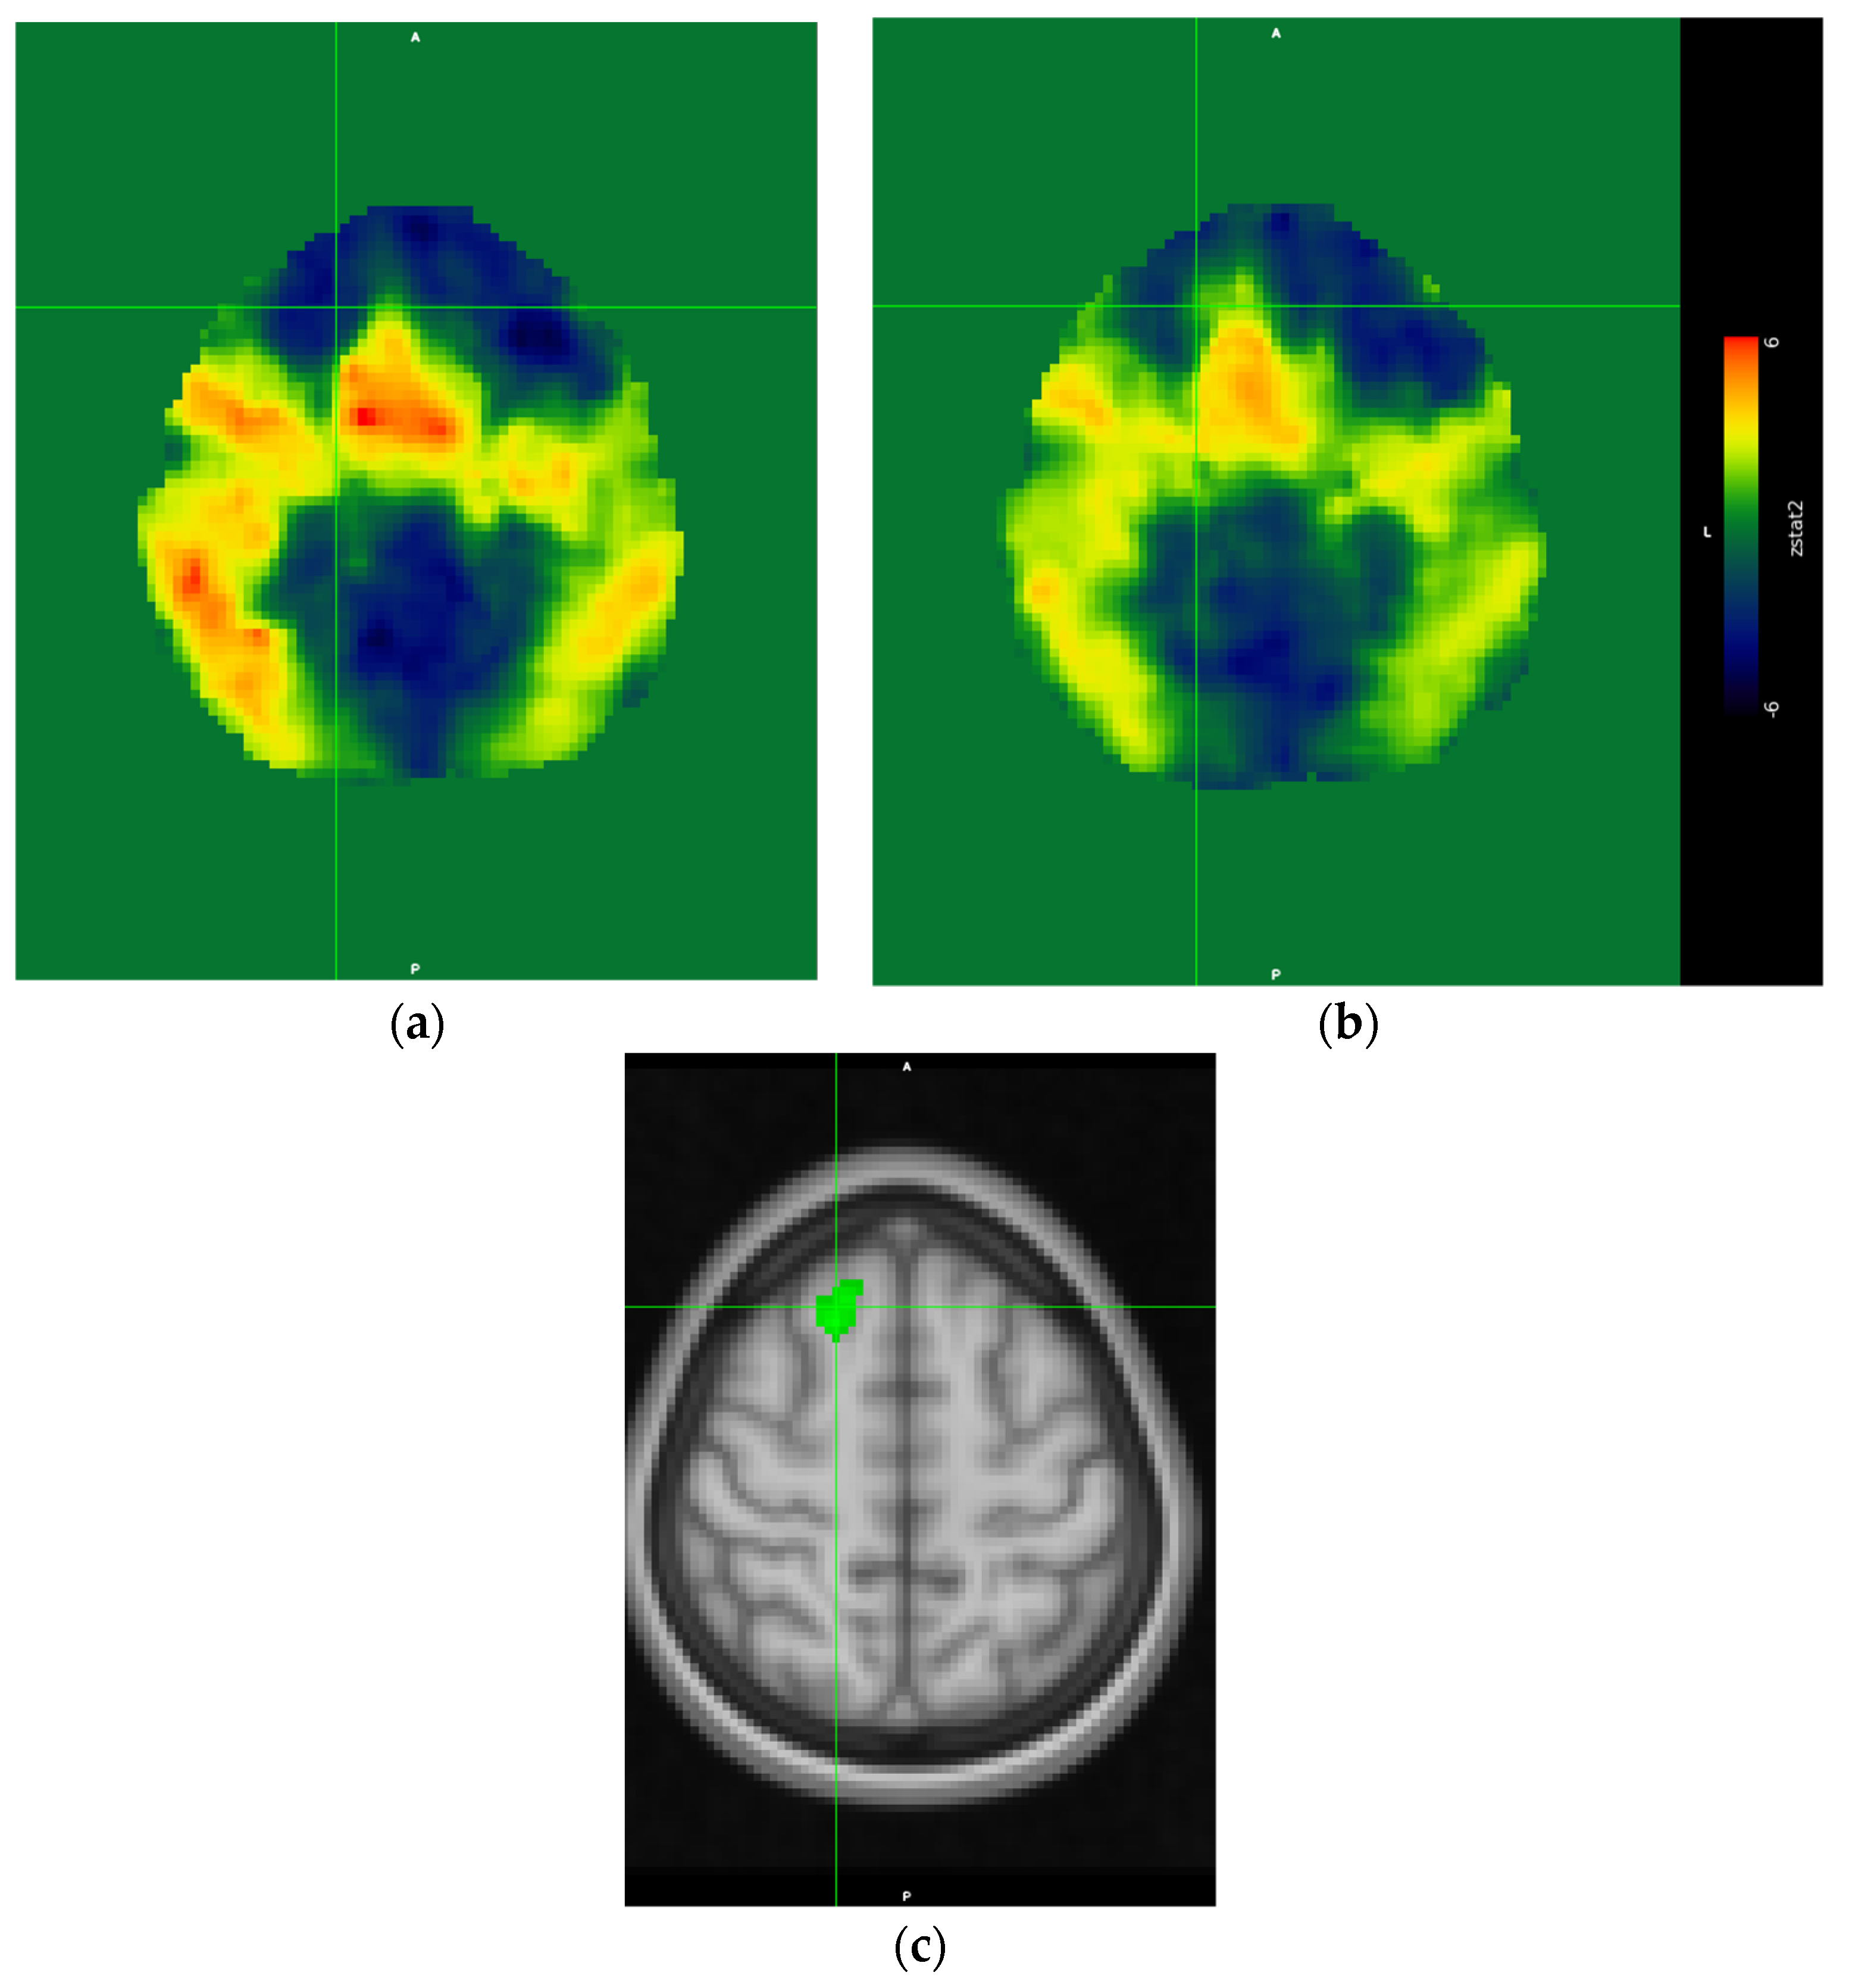

3.3.2. Contrast Results

Direct contrast between both conditions revealed a suprathreshold cluster only in the contrast fatigued > rested. The cluster was located in the right superior frontal gyrus (see Figure 4c). Interestingly, this region did not exceed the Z = 3.1 threshold in either condition, and it appeared in the fatigued > rested contrast because of the negative Z values in the rested condition (see Figure 4a showing the unthresholded Z values) and positive Z values in the fatigued condition (Figure 4b shows the unthresholded Z values). Thus, the difference of activation of this region in both conditions was caused by low response of this region in the rested condition and the moderately elevated response in the fatigued condition.

Figure 4. Unthresholded Z-statistics image of rested condition results (a), unthresholded Z-statistics image of the fatigued condition results (b). Note the larger extension of activations in the rested condition (a) as compared to the fatigued condition (b). The region of statistically significant differences; i.e., the contrast fatigued > rested conditions thresholded at Z > 3.1 (c). The crosshairs indicate the same voxel at the center of the suprathreshold cluster in the right superior frontal gyrus (MNI coordinates: x = 18, y = 26, y = 56, cluster volume = 136, Z-score (maximum—4.53)).

However, at the same time we observed a notable decrease of the extent of activation in the fatigued condition, indicating a less-consistent brain response to the experimental task across participants. Interestingly, we observed a more lateralized pattern of activation in the fatigued condition, with the majority of clusters located within the right hemisphere. We surmised that this effect might be associated with lowered brain metabolism in the state of sleep deprivation [22]. Of course, this does not mean that truck driver’s brain resembles a brain of a dolphin, yet it points to a lowered energy capacity of the fatigued brain, which can affect each hemisphere in a different manner [23]. The direct contrast between conditions revealed only one suprathreshold cluster, obtained in the fatigued > rested contrast. The reverse contrast did not reveal any significant differences. The cluster was located in the dorsal part of the prefrontal cortex. Interestingly, this region did not cross the significance threshold in any of the main effect contrasts for both the rested and fatigued conditions. However, a close inspection of the unthresholded images revealed that in the rested condition, this cluster was strongly deactivated, and in the fatigued condition, the response was positive, yet below the significance threshold. The inspection also revealed that the region discovered in the fatigued > rested contrast was a part of the larger cluster encompassing the medial frontal cortex—covering the SMA, pre-SMA, and parts of the superior frontal gyrus (see Figure 4). Previous research on the effects of cognitive working memory and attentional training research suggested that this region is a part of the cognitive control network, which is engaged in executive control over ongoing cognitive activity, and it is known that its responsiveness becomes significantly decreased over a training period [24,25]. Thus, in our case, the heightened activity of this region might suggest that a relatively simple task we used, involving simple visual feature conjunction detection, in the fatigued condition with lowered metabolic capacity due to sleep deprivation became a task that required more cognitive control resources in order to maintain the performance level. Thus, our results suggested that the influence in the arousal state of drivers on the cognitive level manifested as an increased demand for controlled attentional processing.